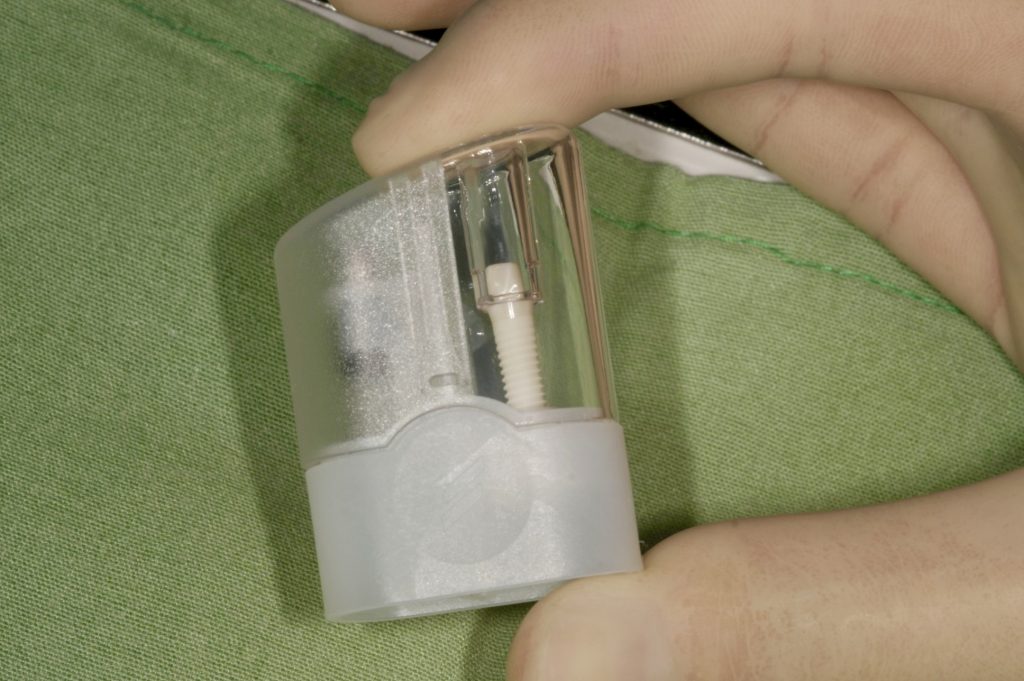

Autores: PRÓLOGO Asimismo, desde el punto de vista pedagógico, el profesional nobel en la materia tiene a su alcance la posibilidad de corregir cualquier posición implantaría en el ordenador, planear los provisionales y plasmarlos en la bio réplica antes de tocar al paciente a operar. Todos estos razonamientos nos llevan a presentar un caso de condiciones muy favorables para poner en práctica estos métodos como primer acercamiento a una Odontología Digital de alta calidad, con medios informáticos, que ya están presentes en la profesión de hoy en día, y será la protagonista única del futuro. Por otro lado, después de numerosos estudios que nos llevan a plantear el “gap” entre implante y pilar(abuttment), como principal responsable de la periimplantitis dado que la microbiota presente en el mismo es imposible de limpiar y en su presencia la cortical ósea reacciona reabsorbiéndose, nos ha llevado a utilizar implantes monobloc ya que los ejes implantarios y protéticos coincidían, y nos permitían su uso. Además, el circonio, ha mostrado a la luz de estudios muy recientes, una preservación y adhesión de los tejidos blandos superiores al titanio, tanto en su tratamiento de superficie de la rosca como a nivel gingival. DESARROLLO Paciente varón de 68 años, con antecedentes de radio/quimioterapia cinco años antes, con Rehabilitación Oral de los cuatro cuadrantes, con una Oclusión Mutuamente Compartida conservada, (REF.8) la que fracasa en el cuadrante 4, 19 años después. El mismo presentaba un puente de porcelana sobre circonio con pilares en 44 y 47, reemplazando el edentulismo de 45 y 46. Se produce la fractura del PM del 44, y ante una endodoncia antigua y corta, se decide implantar las zonas edéntulas, conservando temporariamente los pilares, hasta producida la oseointegración, para entonces también exodonciar el 44. DIAGNÓSTICO Tomamos impresiones del maxilar antagonista, Arco Facial Estático y realizamos montaje del mismo mediante la sistemática ARTEX. Producimos la relajación del músculo Pterigoideo Externo, para obtener la ORC (Oclusión en Relación Céntrica) mediante el método de Laminillas de Long, basado en el concepto de INERVACIÓN RECÍPROCA. Esto nos permitirá montar el maxilar inferior, tanto en su forma de: La primera para practicar la cirugía guiada y comprobar su eficacia, y el modelo de yeso para ser escaneado y confeccionar la GUÍA QUIRÚRGICA. La Biorréplica la obtenemos transformando los archivos DICOM que nos da el CBCT en archivos STL, y a partir de ellos, mediante una tecnología de PROTOTIPADO RÁPIDO, la obtención de un objeto físico en 3D a través de la aglutinación selectiva de una sucesión de capas de polvo. Procedemos a montar la biorrèplica y el modelo de yeso del caso. Podemos verificar la exactitud de las medidas del hueso residual en la bio réplica y compararlas con el scanner. Arrojando un resultado de 8,5 mm de cortical externa a cortical externa. Pudiendo también medir la distancia hasta el dentario. y comparar gracias a la ventana lateral de la biorréplica Dándonos 22mm de distancia. Con lo cual deducimos que implantes de 4,1mm por 12 mm serán perfectamente rodeados de hueso. Medimos también la distancia desde oclusal del antagonista, hasta el hueso desnudo. Lo mismo que, mediante la utilización de la guía radiológica, con un material radiolúcido colocado en gingival de la misma, podemos medir la altura de la encía. Con lo cual podemos calcular la altura del pilar. Es entonces cuando con el programa COC Diagnostix se realiza la programación final: Obteniendo no solo la ubicación, largo, ancho y ángulo de los implantes sino también los provisionales mediante CAD CAM. Ya entonces podemos hacer la práctica quirúrgica en la bio réplica, mediante la guía quirúrgica, instalando los implantes de prueba que no serán los de circonio, ya que la casa no cuenta con ellos, pero si otros de las mismas dimensiones. TRATAMIENTO Entramos ya en la cirugía propiamente dicha. Antisepsia de la zona a operar y zonas anexas. Comprobación del perfecto ajuste e inmovilidad de la G.Q. en boca durante la cirugía. Marcado de la encía y perforación de la cortical. Visión a través de la Guía de la mínima intervención anterior. Comprobación sin Guía. Incisión mínima mesio distal, para apartar y conservar encía queratinizada. Secuencia de drills, perforando a profundidad requerida Observación del Mínimo Trauma Implantes Strauman de Zirconio Monoblock en blíster y montádo en contrángulo reductor. Instalación controlando torque con contrángulo reductor. Comprobación clínica. Comprobación Radiográfica y con Guía. Toma de impresiones, y armado de modelos con técnicas de pasividad protética. Montaje. Resultado de las provisionales ejecutadas por CAD CAM Al no estar conformes con el resultado decidimos desechar dichas provisorias y optar por repetirlas. Nuevas provisorias realizadas mediante encerado convencional. Estado de los tejidos blandos. Provisorias en boca. Oclusión de Estímulo Inmediato. Ref.10: Carga inmediata .Alberto y Diego Bechelli. Comprobación mediante CBCT post operatorio Componentes del equipo (En la próxima presentación, mostraremos las coronas definitivas de porcelana sobre circonio, y la desoclusión provocada por una OCLUSIÓN MUTUAMENTE COMPARTIDA, sobre estos implantes y otros seis mas) REFERENCIAS

Fig. 9

Fig. 10

Fig. 11

Fig. 12

Mas adelante, y por cuestiones de conveniencia protética, el implante instalado del premolar será de 3,3 mm.

FIG: 35-36-37-38-39-40-41

Fig. 35

Fig. 36

Fig. 37

Fig. 38

Fig. 39

Fig. 40

Fig. 41